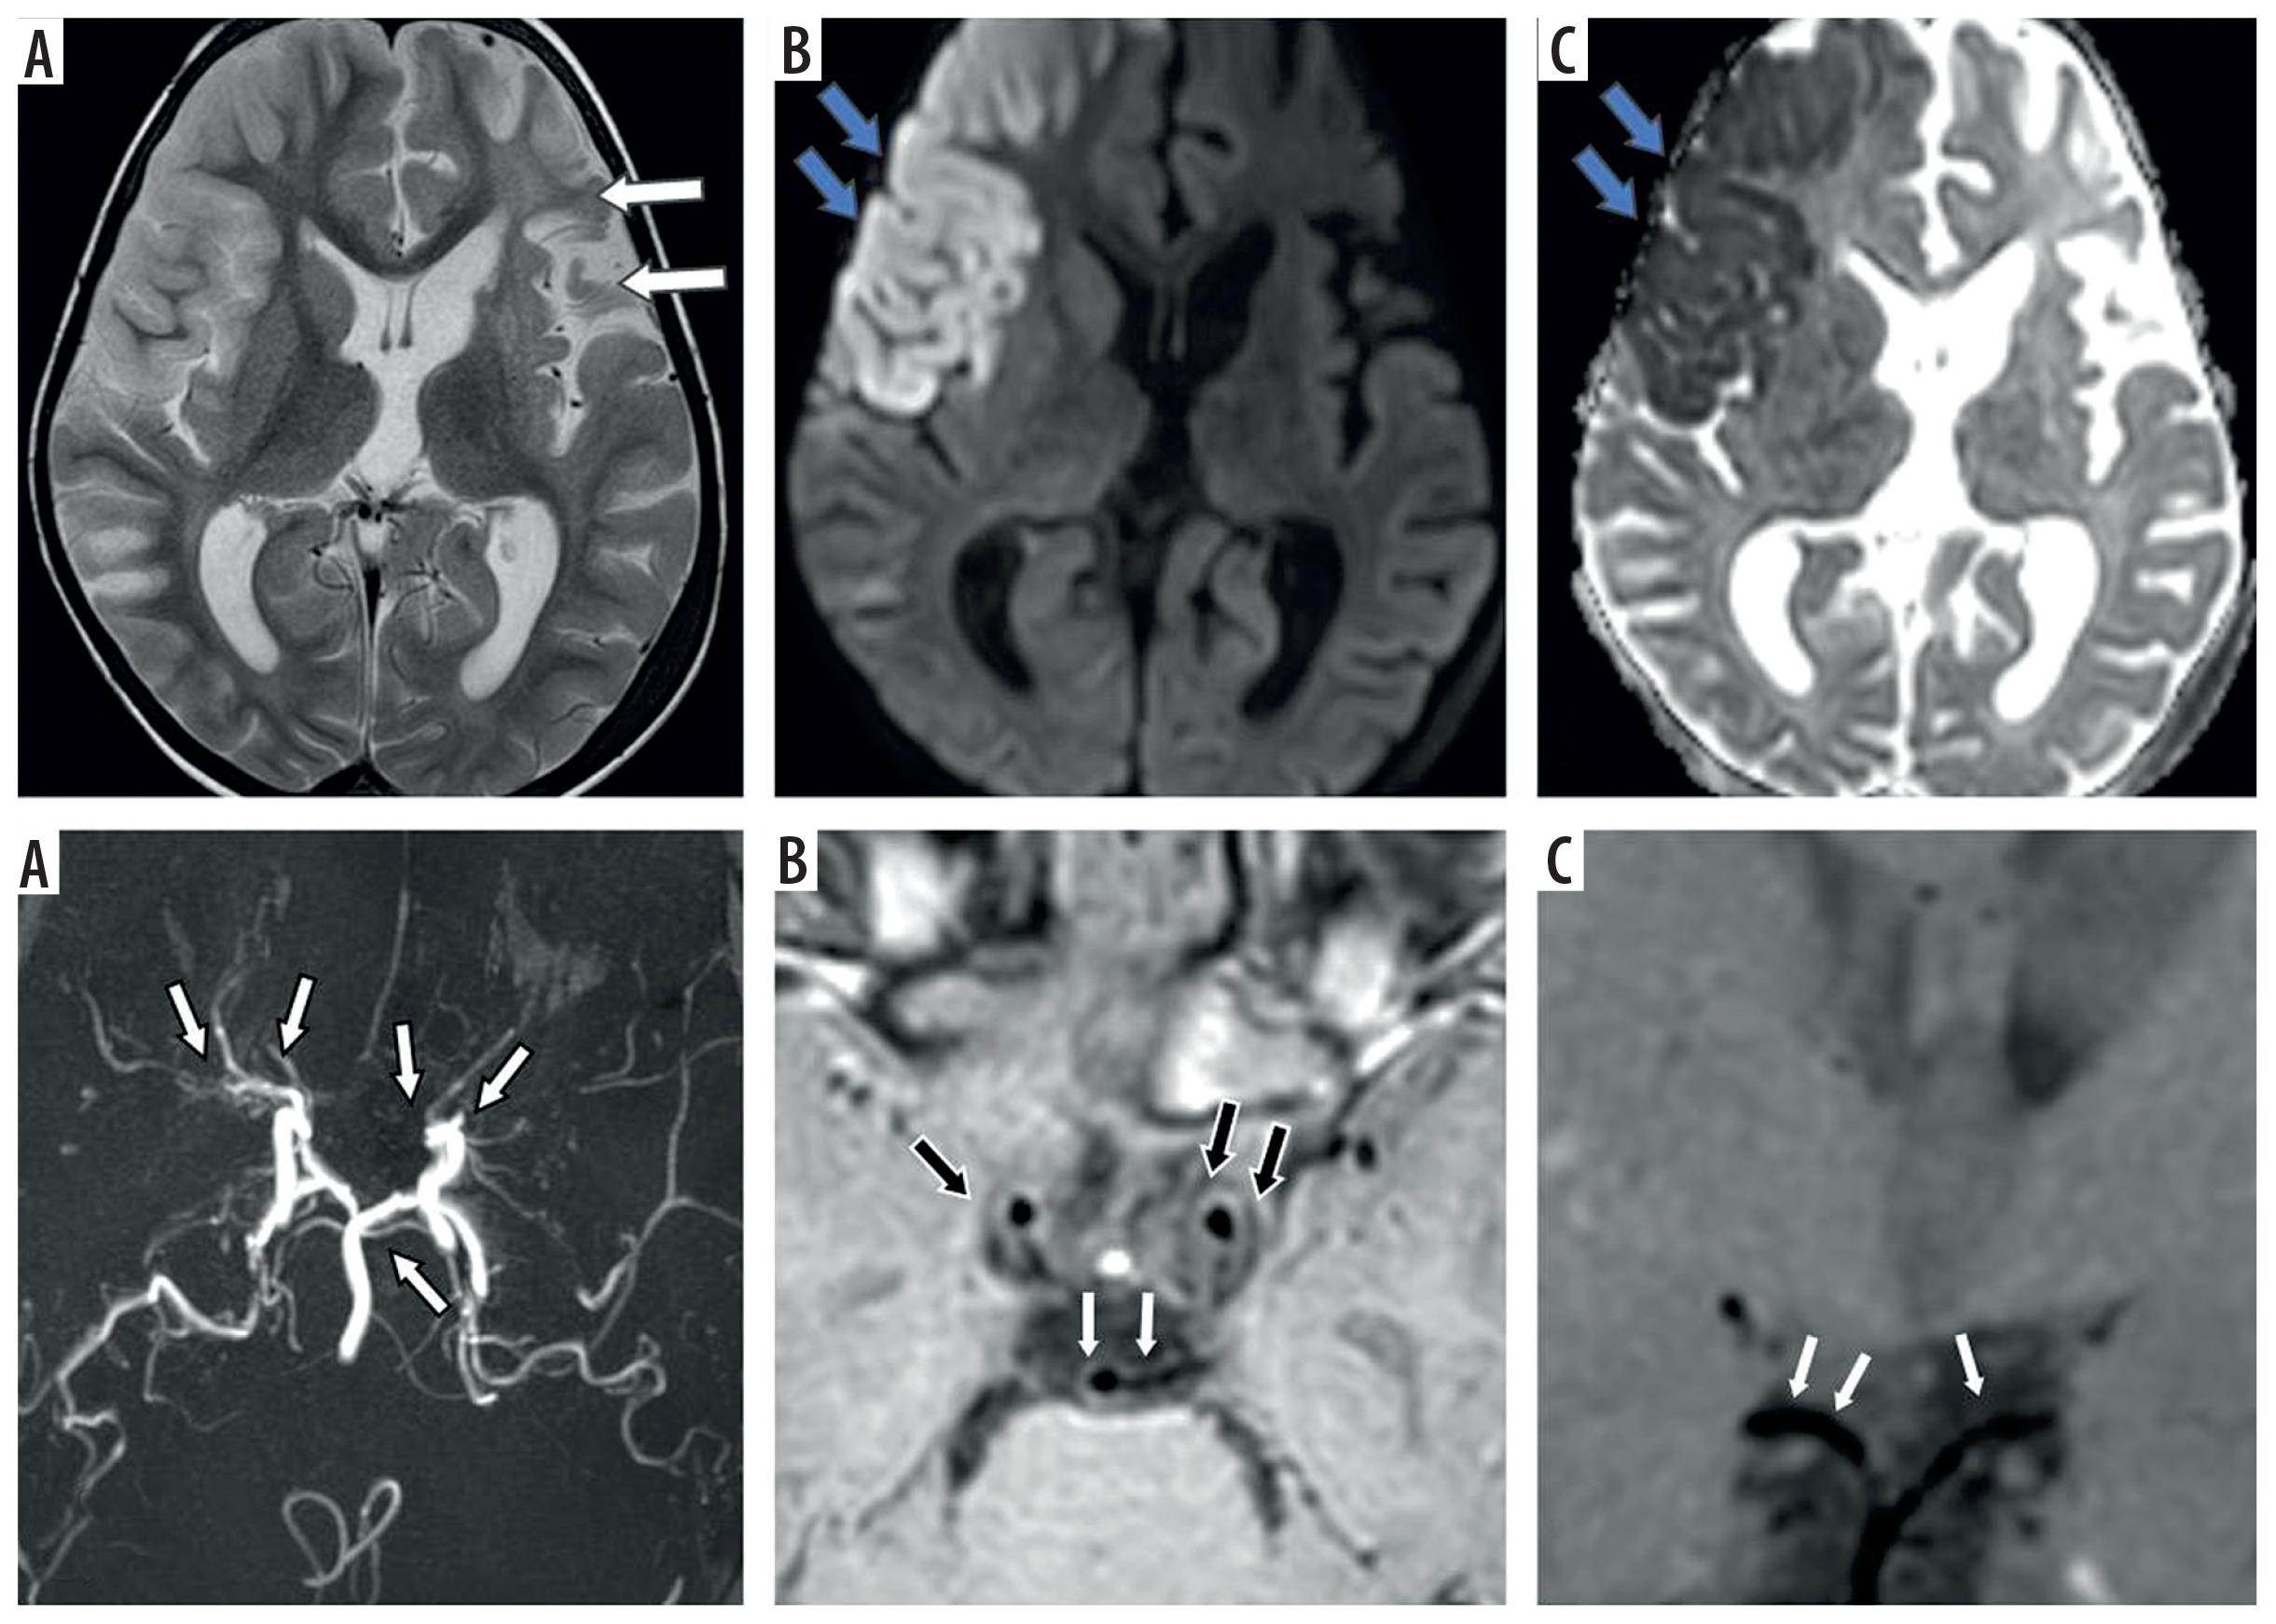

Figure 2

Fifteen-year-old female presenting with right sided hemiparesis. Axial T2 (A), axial diffusion-weighted imaging (B) and axial apparent diffusion coefficient map (C) images show volume loss with mild encephalomalacia in left parieto-occipital region (white arrows in A) along with few areas of diffusion restriction in left temporo-occipital region (blue arrows in B and C). Coronal anterior view maximum intensity projection time-of-flight magnetic resonance angiography (MRA) image (D) shows stenotic left supraclinoid internal carotid artery (ICA) with occluded left terminus ICA and left middle cerebral artery (MCA) (white arrows in D). Coronal post-contrast vessel wall imaging (VWI) (E) and axial post-contrast VWI (F) showing vessel wall thickening and grade 1 concentric enhancement of left supraclinoid, terminus ICA, left MCA and anterior cerebral artery (black arrows in E and F). Grade 1 concentric enhancement is also noted in right supraclinoid, terminus ICA and right MCA (white arrows in E and F)

Figure 3

Three-year-old female presenting with right sided hemiparesis for 2 months with recurrent right focal seizures. Axial T2 (A), axial diffusion-weighted imaging (B) and axial apparent diffusion coefficient map (C) images show volume loss in right fronto-parietal region (white arrows in A) with a few foci of diffusion restriction in left parieto-temporal region with cortical diffusion restriction in left frontal lobe (blue arrows in B and C). Coronal anterior view maximum intensity projection time-of-flight magnetic resonance angiography (MRA) image (D) shows stenotic right supraclinoid internal carotid artery (ICA), right terminus ICA, right anterior cerebral artery (ACA) and right middle cerebral artery (MCA) and also left supraclinoid ICA (white arrows in D). Coronal oblique post-contrast vessel wall imaging (VWI) (E) and axial post-contrast VWI (F) showing vessel wall thickening and grade 1 concentric enhancement of right supraclinoid, terminus ICA, right MCA and ACA (black arrows in E and F). Grade 1 concentric enhancement is also noted in left supraclinoid, terminus ICA and left MCA and ACA (white arrows in E and F)